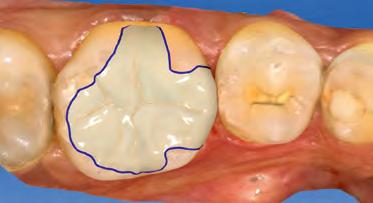

Immédiatement après le processus d’usinage, l’inlay fini est essayé en bouche pour vérifier sa bonne adaptation avec la substance résiduelle de la dent naturelle (Fig. 4).

04 — Contrôle général et de la teinte de l’inlay usiné